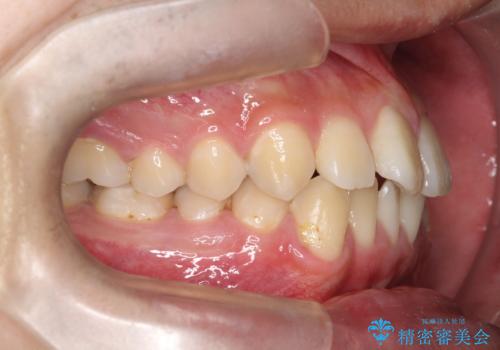

【ワイヤー矯正】前歯の凸凹を治したい。

- 前歯の凸凹を主訴に来院されました。

患者様がマウスピース矯正の使用時間に不安があるため、ワイヤー矯正にて治療を行なっております。